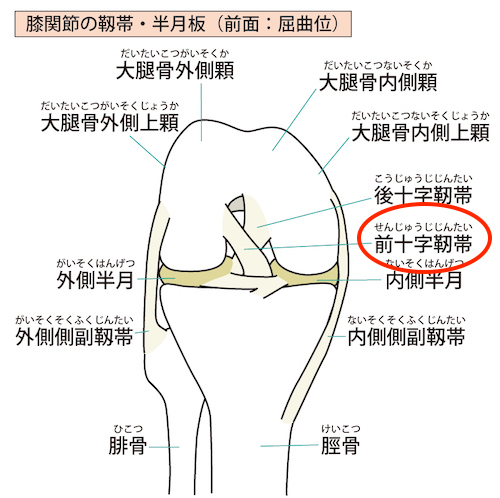

膝前十字靭帯損傷 症状 診断 治療について 足立慶友整形外科